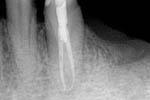

Revisionsbehandlung eines Unterkiefermolaren (37) vor geplanter Überkronung (Dr. Maik Göbbels) Download